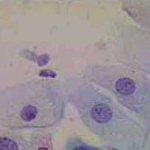

Δυσπλασίες τραχήλου μήτρας σοβαρού βαθμού (CIN III)

Ασυμπτωματική ασθενής 39 ετών. PH κόλπου 4,4. Κολποσκόπιση:

Στην δοκιμασία οξικού οξέως και στην δοκιμασία Lugol, αρνητική περιοχή, τόσο στο πρόσθιο, όσο και στο οπίσθιο χείλος του τραχήλου, σε ακτίνα 3-4 χιλ. και πλάτος περίπου 5 χιλ., με εικόνα διακριτικού επίπεδου μωσαϊκού.